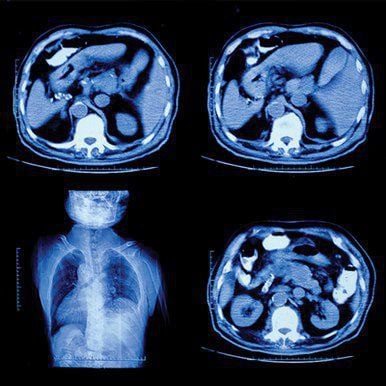

Designed for both the general and specialized radiologist, UCSF Abdominal and Thoracic Imaging is an online CME course providing an extensive review of clinically relevant topics in chest, abdominal, pelvic, and ob-gyn imaging. Speakers discuss interpretation tips for both routine and emerging applications, artificial intelligence and its implications in clinical practice, and more.

You get case-based continuing medical education lectures targeting relevant areas of focus, including:

- Abdominal — female pelvis, acute pelvic pain in the reproductive age female, early and ectopic pregnancy, male pelvis and prostate, gastrointestinal conditions including the liver, and organ transplants

- Thoracic — lung cancer screening, pulmonary embolism, mediastinal masses, chest radiographs, and other findings and indications relevant for the general radiologist